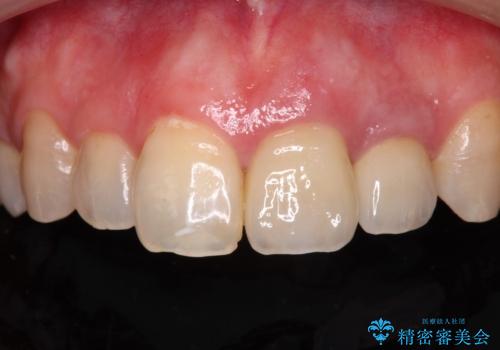

仮歯を装着した時点で、口元が気にならなくなったので、患者様が感じていた違和感の原因は変色した前から2番目の歯であったと思われます。

形態や色彩が左右対称となるように仕上がり、患者様には大変満足していただきました。